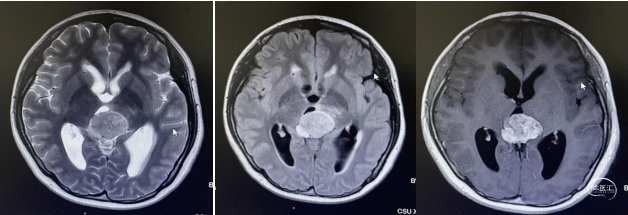

头部磁共振:松果体区可见一稍长-长T1、稍长-长T2信号灶,内可见小片状短丁1信号,增强后实性成分明显不均匀强化,大小约30mmx24mmx33mm,病灶部分伸入第三脑室,第三脑室扩张,双侧丘脑受压移位,中脑导水管,以慕上脑室系统积水扩张,双侧脑室旁可见线样FLAIR高信号。左侧丘脑,左侧脑桥及桥臂可见小片状长T1长T2信号,FLAIR呈高信号。